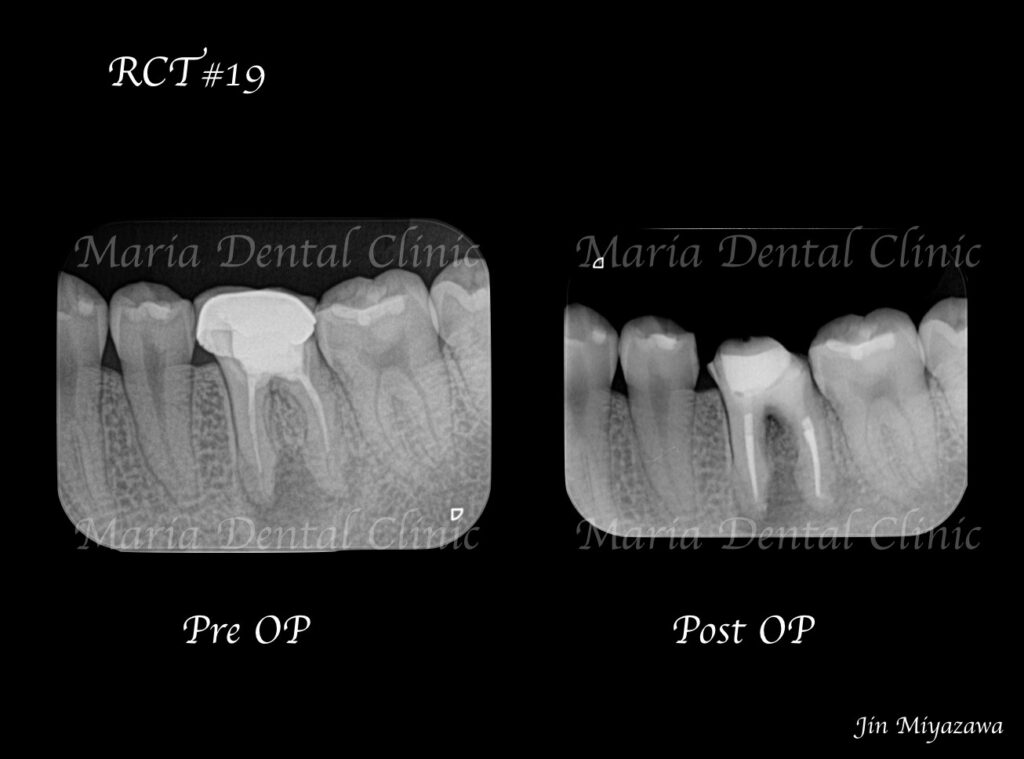

歯肉が腫れと痛みを訴え来院された患者様です。症状、レントゲン、ポケット診査より根尖性歯周炎と診断。 診査時には触ることでの痛み、限局的な歯周ポケットを確認しました。

顕微鏡下にて、軟化象牙質(虫歯)や根管内充填物を綺麗に除去し、貼薬を1週間行いました。

1週間後、痛みと腫れは消失しました。

経1ヶ月後の経過観察で治癒過程が確認できれば、可及的速やかに最終補綴物の製作に移行します。

3ヶ月後に再度経過観察を行い最終的な根管治療の予後を確認する予定です。